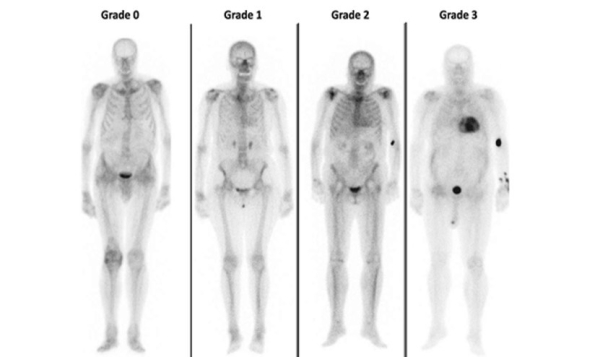

Le score de PERUGUINI utilisé dans l’amylose permet une évaluation semi-quantitative de l’intensité de fixation du traceur osseux dans le myocarde1 (Figure 6).

- Grade 0 : absence de fixation cardiaque du traceur

- Grade 1: fixation cardiaque faible < au signal des côtes

- Grade 2: fixation cardiaque = au signal des côtes

- Grade 3: fixation cardiaque > au signal des côtes associée à une diminution de la fixation globale osseuse du traceur

Figure 6 : Scintigraphie osseuse